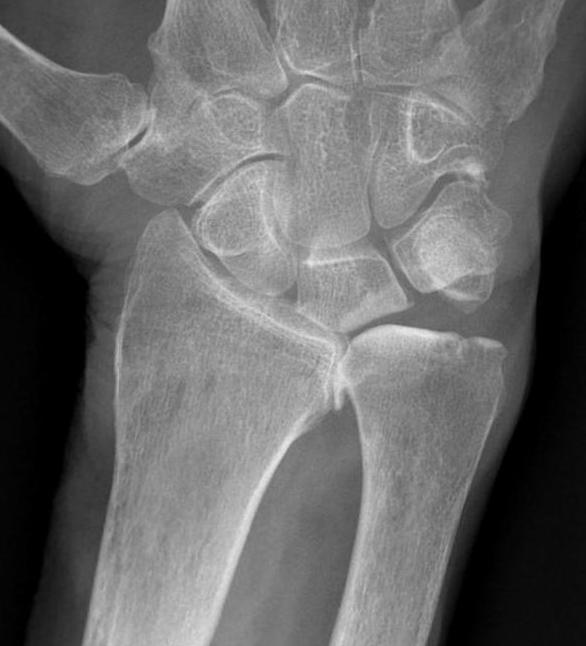

Darrach's

- distal ulna excision

- best for elderly RA patient